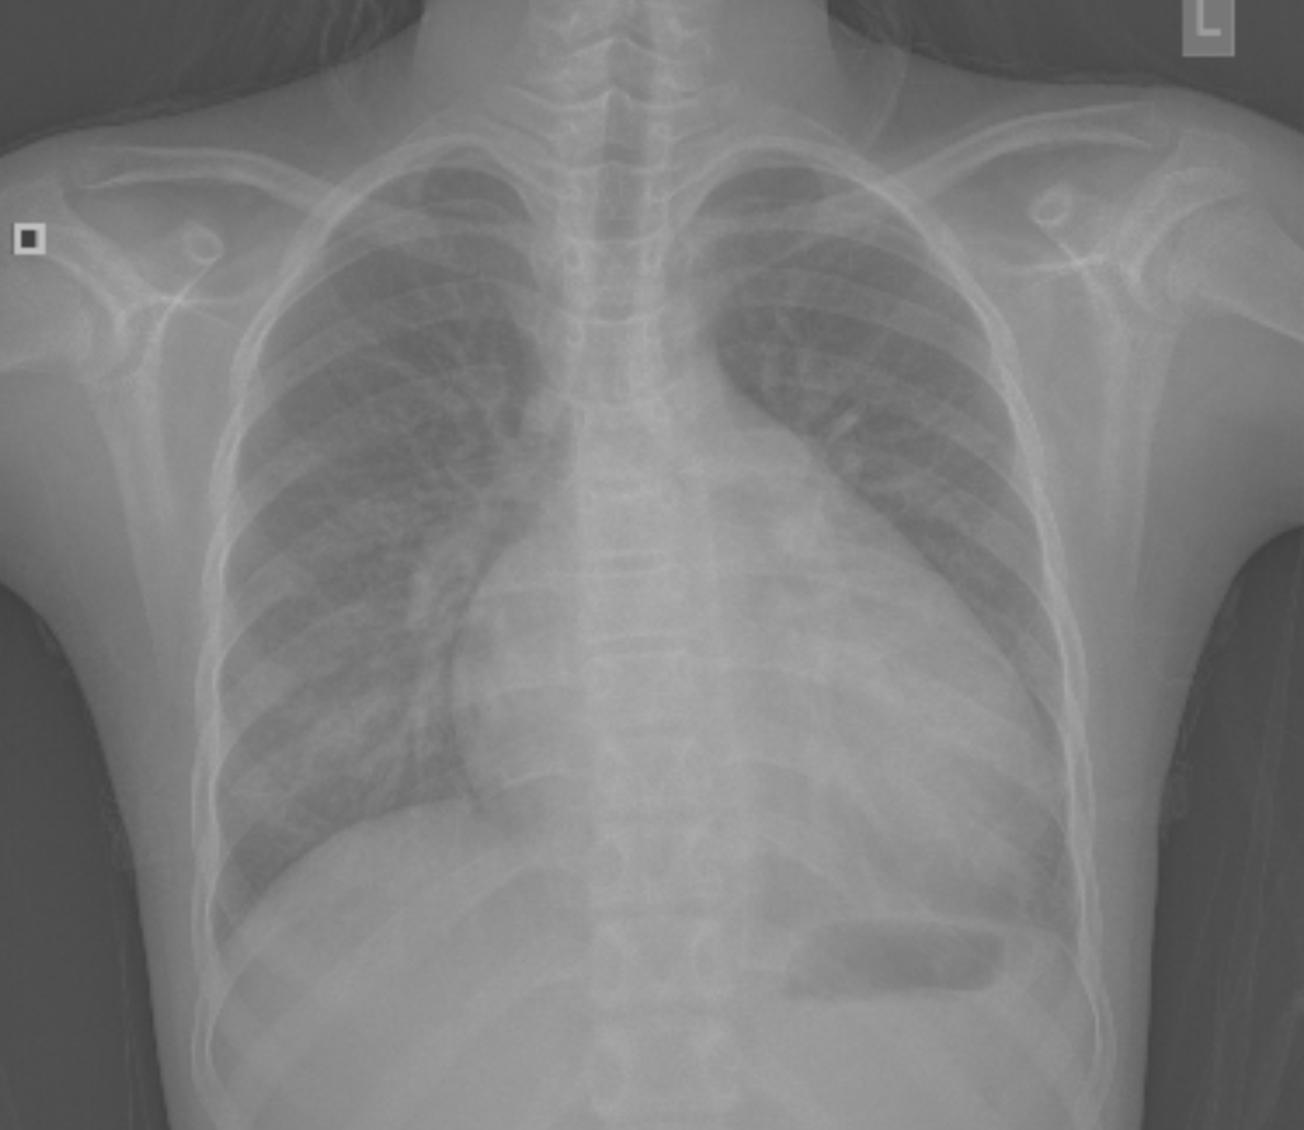

在一个阳光明媚的早晨,主人公李明如往常一样被鸟儿的歌声唤醒,他患有扩心病,但今天的心情格外轻松,因为他即将接受最新的扩心病治疗。

医生告诉他们,最新的扩心病治疗技术已经取得了很大的进展,这种治疗方法结合了先进的医疗技术和个性化的护理方案,旨在帮助患者恢复心脏功能,提高生活质量。